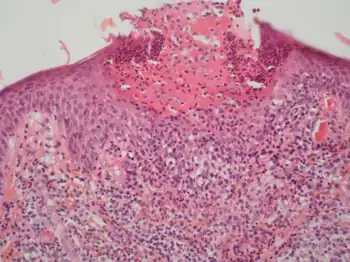

The diagnosis of AGEP may be forthright in typical cases in which an individual: has taken a drug known to cause the disorder; develops multiple sterile pustules overlying large areas of red swollen skin starting a few days after initial drug intake; and has a histology of biopsied lesions that shows pustules just below the skin's Stratum corneum (outermost layer), apoptotic (i.e. necrotic) keratinocytes, spongiosis of the stratum spinosum, and infiltration of these tissues by neutrophils plus, in many but not all cases, eosinophils.[7] Many cases of AGEP, however, present less clear cut clinical features of the disorder. AGEP must be differentiated from generalized pustular psoriasis (GPP) with which it shares many clinical and histological features. A history of psoriasis, the presence of typical psoriatic skin lesions at the time of diagnosis, and histological evidence in skin lesions of necrotic keratinocytes, neutrophil-rich infiltrates, eosinophil infiltrates, and/or lack of tortuous or dilated blood vessels favors a diagnosis of to AGEP.[20] Other conditions sometimes confused with AGEP include pustular eruptions caused by bacteria, funguses, herpesviridae, and the varicella zoster virus (i.e. causative agent of chicken pox).